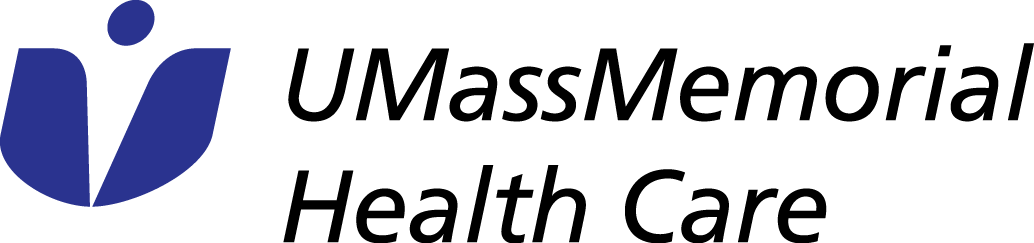

CT is still an important tool in pediatric diagnosis. New technology has evolved to dramatically lower the radiation dose of CT scans in children. Additionally, the CT scans can now be performed very quickly. In the past, some children would need to be sedated with medication in order to insure that they could hold still long enough for the test to be performed. The new ultrafast CT scanners are so fast that sedation is often unnecessary.

3D reconstruction of a CT scan in a patient with a double aortic arch squeezing the trachea (windpipe) causing him breathing difficulty.

3D reconstruction of a CT scan in a patient with a double aortic arch squeezing the trachea (windpipe) causing him breathing difficulty.